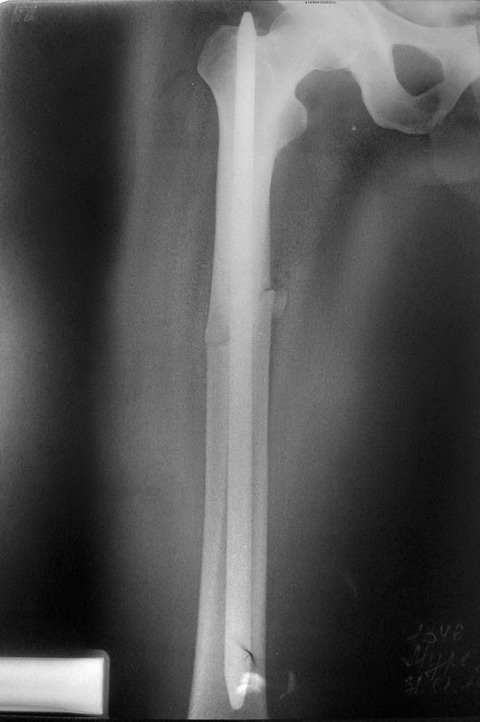

Это не повторный перелом, а несостоятельная фиксация. А почему диафизарный перелом бедра синтезирован пластиной, а не закрыто гвоздем? Ответ на этот вопрос нужен, чтобы думать над тем, что делать дальше.

Пациент приехал к нам из далекой глубинки, может поэтому выбран накостный остесинтез в качестве приоритета. Если же брать по науке АО, то учитывая, простой характер перелома, абсолютная стабильность в данном случае, как мне кажется, оптимальна и поэтому судить о правильном количестве винтов затруднительно. Сказать, что этот остеосинтез некорректен на 100% нельзя. Были случаи и похуже.. А вот почему произошел перелом на фоне, практически, отсутствия нагрузки - это вопрос.

Здравствуйте глубокоуважаемые коллеги! Согласен с Александром Николаевичем Челноковым по-поводу:

1. Почему не выбран первоначально ЗИМО бедра стержнем с блокированием? а также БИОС большеберцовой кости? Хотелось бы увидеть R-графию перелома голени и стопы.

2. Почему выбрали именно такое сочетание остеосинтеза бедра и голени (пластина на бедро и АВФ на голень)? Получается, что вся масса н/конечности ниже перелома бедра держится на пластине с винтами...

Здравствуйте!

Для этого перелома пластина абсолютно не подходит, т.к. по внутренней поверхности, если я хорошо увидел имеется оскольчатый перелом, таким образом кость не "защищает" пластину, а наоборот, вызывает сильную нагрузку на варус. В таких случаях очень часто наступает дебриколяж (перелом пластины), в Вашем случае перелом винтов. Вы и сами видите, что после перелома фрагменты приняли варусное положение, сместившись в зону дефекта, фрагменты к этому стремились, они этого добились. Кроме этого пластина слишком короткая, нужно было накладывать практически на весь диафиз. Обязательно нужно было делать костную пластику по внутренней поверхности бедра в месте оскольчатого перелома и производить межфрагментарную компрессию. Но стоило ли это таких усилий? Поэтому, только ЗИМО.